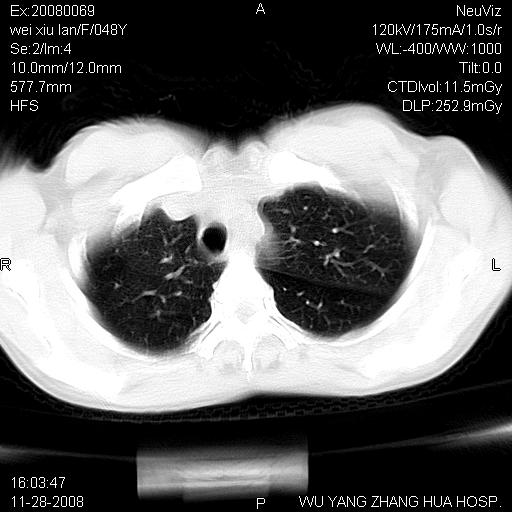

标题: CT16847:女,48岁,咳嗽,发热两日,平常偶有上腹部不适。 [打印本页]

标题: CT16847:女,48岁,咳嗽,发热两日,平常偶有上腹部不适。

能否考虑食管裂孔疝?请老师们多多指教。